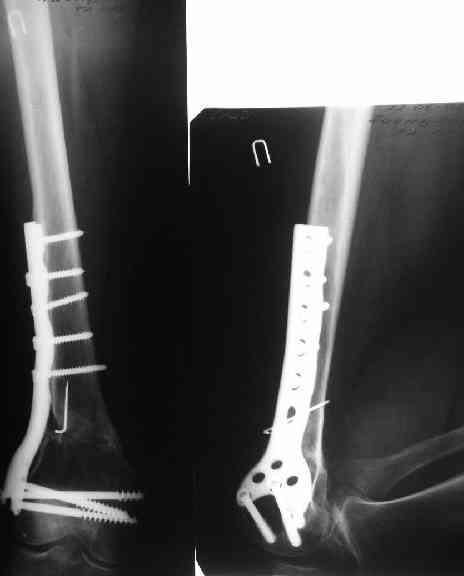

В приложении пример, как их использовали после остеотомии бедра по поводу сросшегося с вальгусом перелома, чтобы не дать гвоздю уйти во внутренний мыщелок.

Да, действительно красивый клинический пример: виден вальгус до операции и последующая коррекция углового смещения на "полярах". Я так понимаю, что в вашей клинике есть возможность использовать различные фиксаторы. Почему не использовали DFN? Спицы какие используете? Киршнера или Илизаровские? С виду очень тонкие...